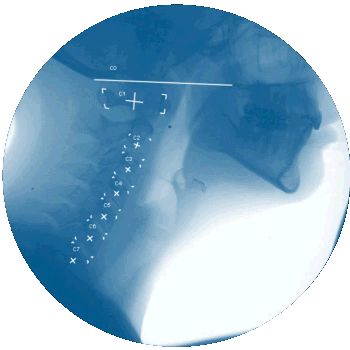

The Vertebral Motion Analysis (VMA®) goes beyond static images, offering a dynamic view of the spine in motion

providing a greater opportunity of detecting this objective biomarker.

The VMA reveals spinal injuries and instabilities that might be invisible on a standard X-ray or MRI. Here's why:

Spinal Analysis: Measures angulation, translation and disc height of the cervical and lumbar spine.

"Spinal Movie": Watch the spine move in real-time.